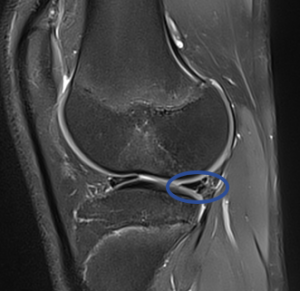

Lorsqu’une lésion méniscale est suspectée, une IRM est demandée. Cet examen est très sensible et permet de préciser l’existence ou non d’une lésion méniscale et d’évaluer l’état ligamentaire également. La lésion est décrite: localisation (sur le ménisque), type et étendue. Il sera souvent nécessaire alors d’envisager une chirurgie.

![]() véritable lésion verticale d’un menisque |

PARTICULARITE CHEZ L’ENFANT: L’IRM est délicate à interpréter sur le plan méniscal: la présence de vaisseaux dans le ménisque (qui ont disparu chez l’adulte) peut être interprétée à tort comme une lésion méniscale. |